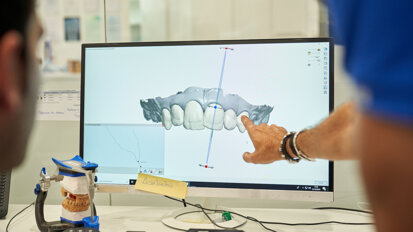

W przypadku znacznej atrofii żuchwy możliwe jest zastosowanie krótkich implantów i wykonanie zadawalającego estetycznie i funkcjonalnie ...

Na temat estetycznych uzupełnień protetycznych i trendach we współczesnej stomatologii estetycznej rozmawiamy z dr. Maciejem Żarowem.